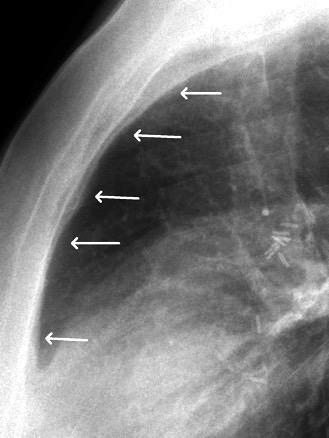

En el normal, el bronquio intermediario (BI) aparece en la proyección lateral, como una línea fina vertical que cruza el bronquio del LSI en su unión con el principal. (BPI) Engrosamiento del bronquio intermediario (BI)

97% de normales

Causas

Fallo cardiaco

Ca de pulmón

Metástasis

Linfoma

Sarcoidosis

Castleman

Schnur MJ et al.. Thickening of the Posterior Wall of the Bronchus Intermedius. Radiology. 1981

MJ et al.. Thickening of the Posterior Wall of the Bronchus Intermedius. Radiology. 1981 Ca. microcítico